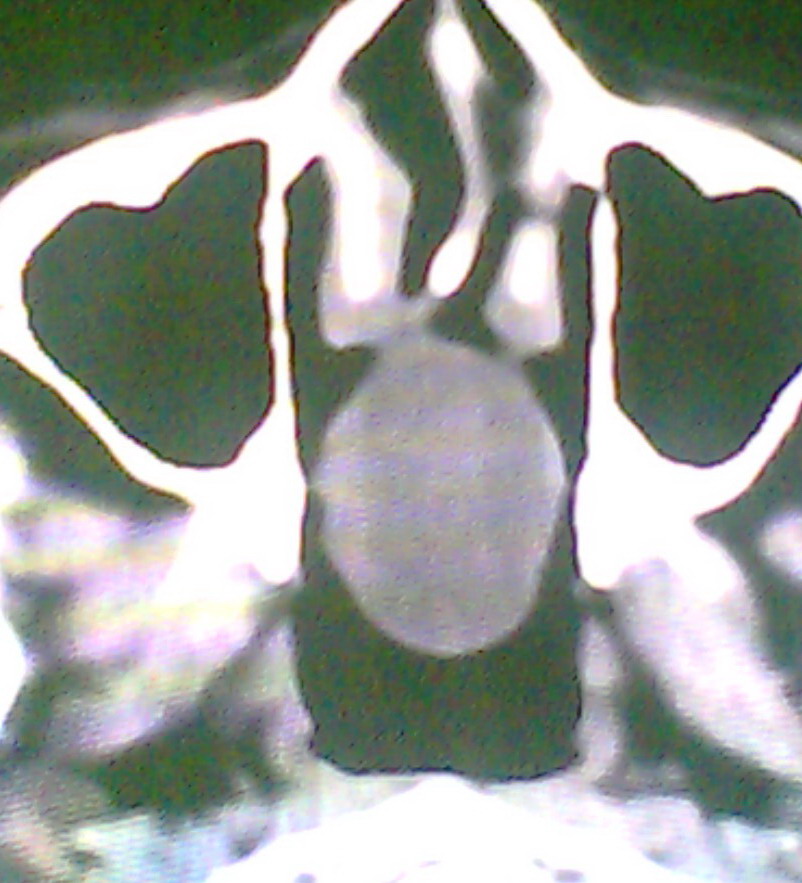

女、18岁,身高1.5左右,鼻塞、流涕数月,两侧瞳孔明显增大,曾与几年前去北京看眼,未发现病变。

考虑起源与蝶窦的粘液囊肿。

考虑起源于蝶窦的粘液囊肿突入鼻咽部。

\"几年前去北京看眼\"不知这句话有何玄机,支持考虑脑膜脑脊液鼻内膨出,膨出口在蝶鞍处

在上级医院冠状位ct扫描后,诊断为:脑膜膨出,已住院准备手术。等待术后结果。